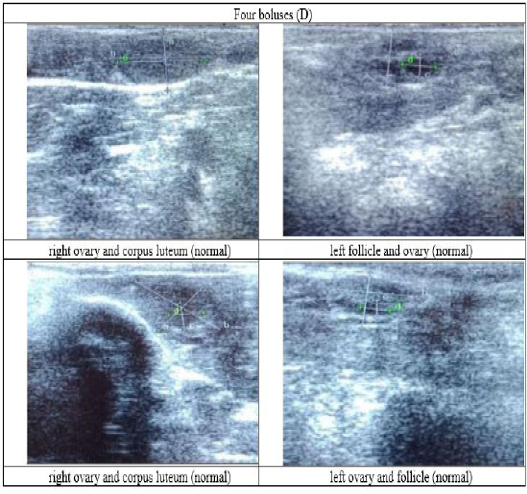

Figure 6

Ultrasound observation of the reproductive tract of crossbred cows received four boluses (D).